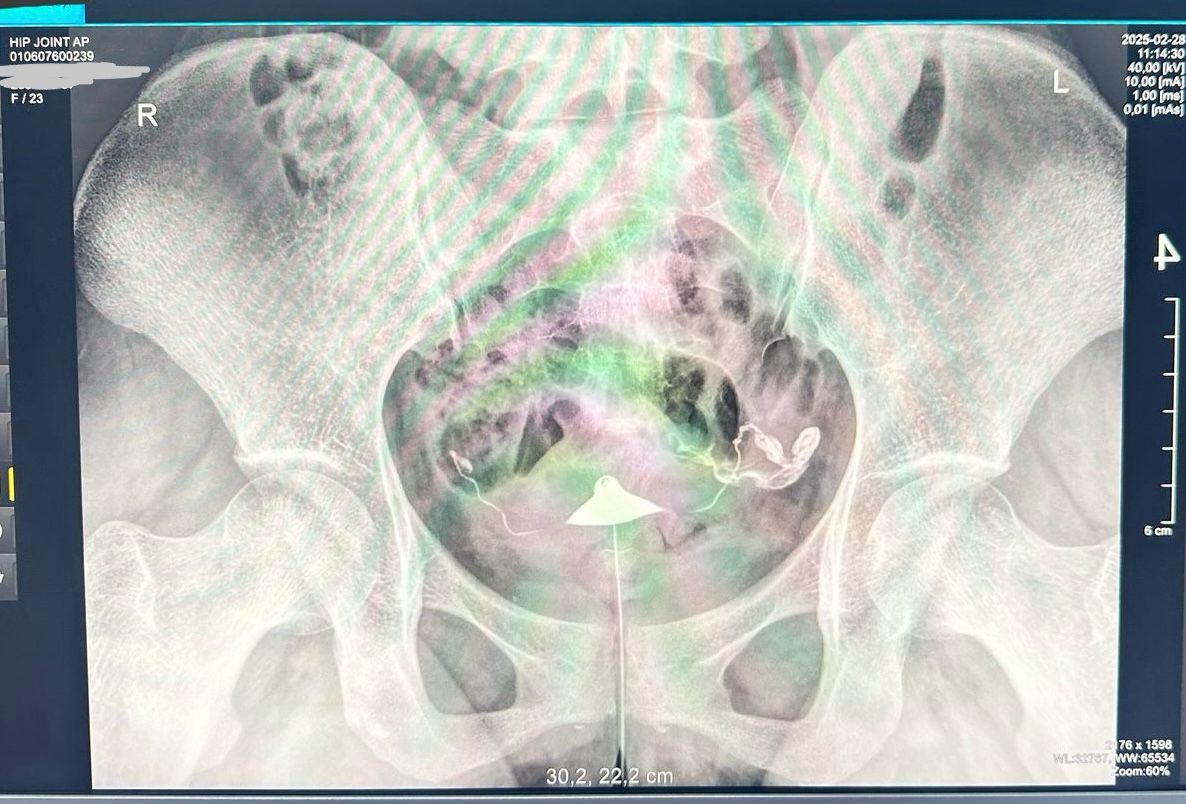

Девочки, делала сегодня ГСГ рентген, сказали трубы проходимы, но в заключении написали двухсторонний сактосальпинкс. У кого было подобное?

ГСГ, Сактосальпинкс